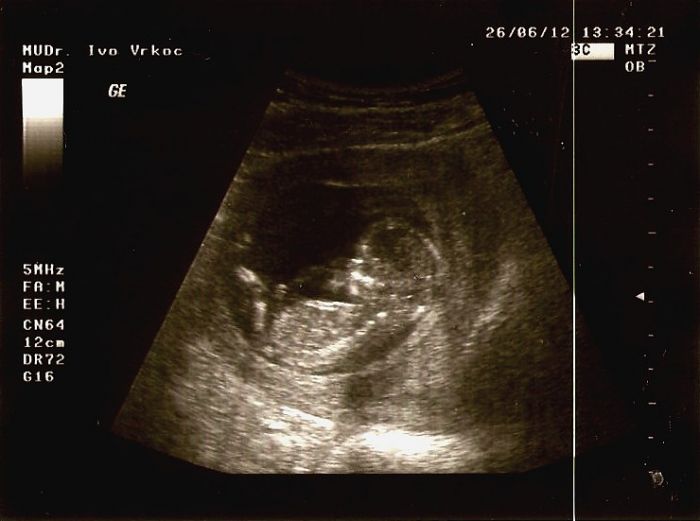

Ahojky, dlouho jsem tu nebyla a koukám že je tu spoutu nových fotek a příspěvků. Smile Já se vrátila z dovolené a v pondělí jsem byla na tom screeningu +NT. Miminko je v pořádku a korát byl nějaký problém, že mám moc protilátek proti bakteriím, ale už je to dobrý. Jinak se nám zase posunul TP už vychází na 1.1.2013 Sealed Takže bych tady už vlastně neměla býtSealed a taky přidávám nejnovejší fotečku ze 13+6 tt